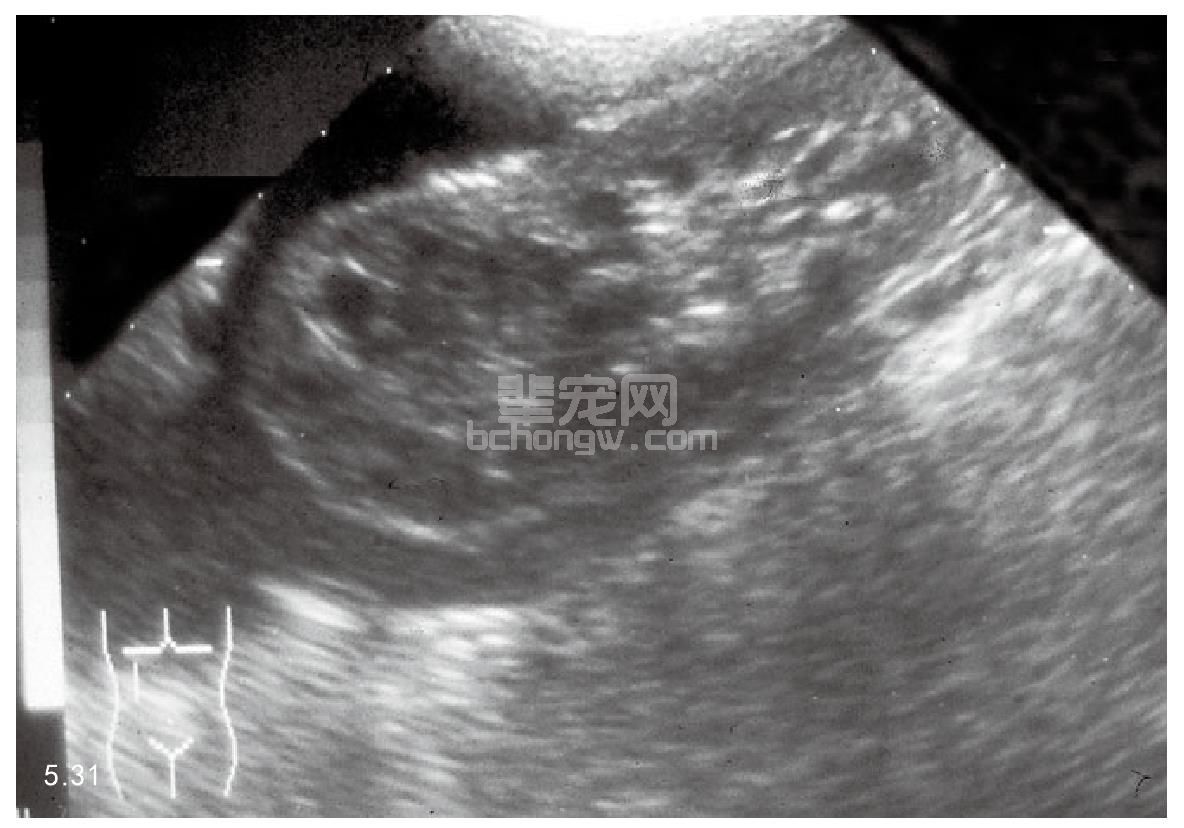

图5.31 超声波检查犬的肾脏肿瘤。